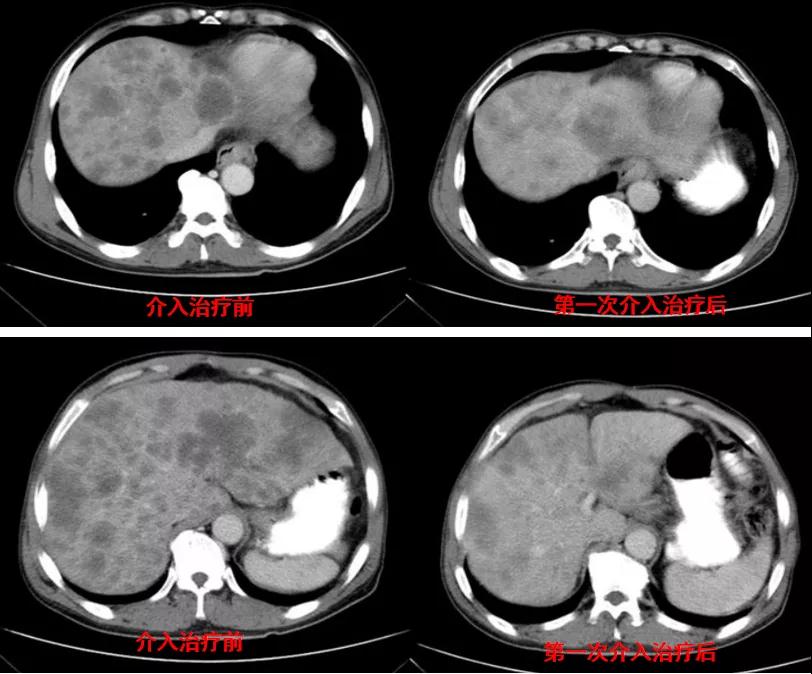

诊治经过:2020年11月25日患者行经皮动脉化疗灌注栓塞术(铂类+氟尿嘧啶);2020年11月30日免疫组化及基因检测结果为:ERBB-2扩增(9倍),VEGFR未突变,MSI微卫星低度不稳定,错配修复蛋白部分缺失(dMMR),MSH2(+弱),MLH1(-),MSH6(+),PMS2(-),CDX2(-),Villin(+),CK8/18(+),Ki67(5%+),CD56(-),Syn(-),CgA(-);患者为HER2阳性,患者肝脏病灶很多,残余正常肝脏体积小,需要寻找对肝功能影响小且抗瘤效果明显的治疗,因此联合吡咯替尼进行系统治疗。2020年12月14日复查结果提示肝脏病灶明显缩小(PR)。结果见图2。

图2

诊治经过:2020年12月16日患者行第二次经皮动脉化疗灌注栓塞术(铂类+氟尿嘧啶)治疗,并继续联合吡咯替尼治疗。结果见图3。

图3